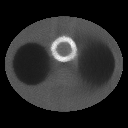

Refer to caption Refer to caption

Figure 1: activity map(left) and attenuation map(right).

In this section we investigate the performance of the proposed algorithms by several numerical experiments of SPECT reconstruction. To this end, and the projection data were generated based on the following model. As shown in figure 1, the activity phantom consists of an ellipsoidal background (body region) with axes of length 22.5cm and 30cm, which contains two smaller ellipsoidal regions(lungs) with axes of length 10cm and 8.8cm, and a ring(myocardium) of inner and outer diameters 6cm and 8cm, respectively. The activities in myocardium, background, and lungs are specified to be in the ratio 3:2:1.

To simulate the attenuation coefficient in chest, we utilized the phantom used in [10], which imitates a section of human thorax. Besides the body background and lungs, the attenuation map consists of two circular regions (bones) of diameter 2.5cm(see figure 1). The attenuation coefficients were 0.03cm-1 within ’lung’ regions, 0.17cm-1 within ’bone’ regions, 0.15cm-1 elsewhere within the body ellipse, and 0.00cm-1 outside the body.